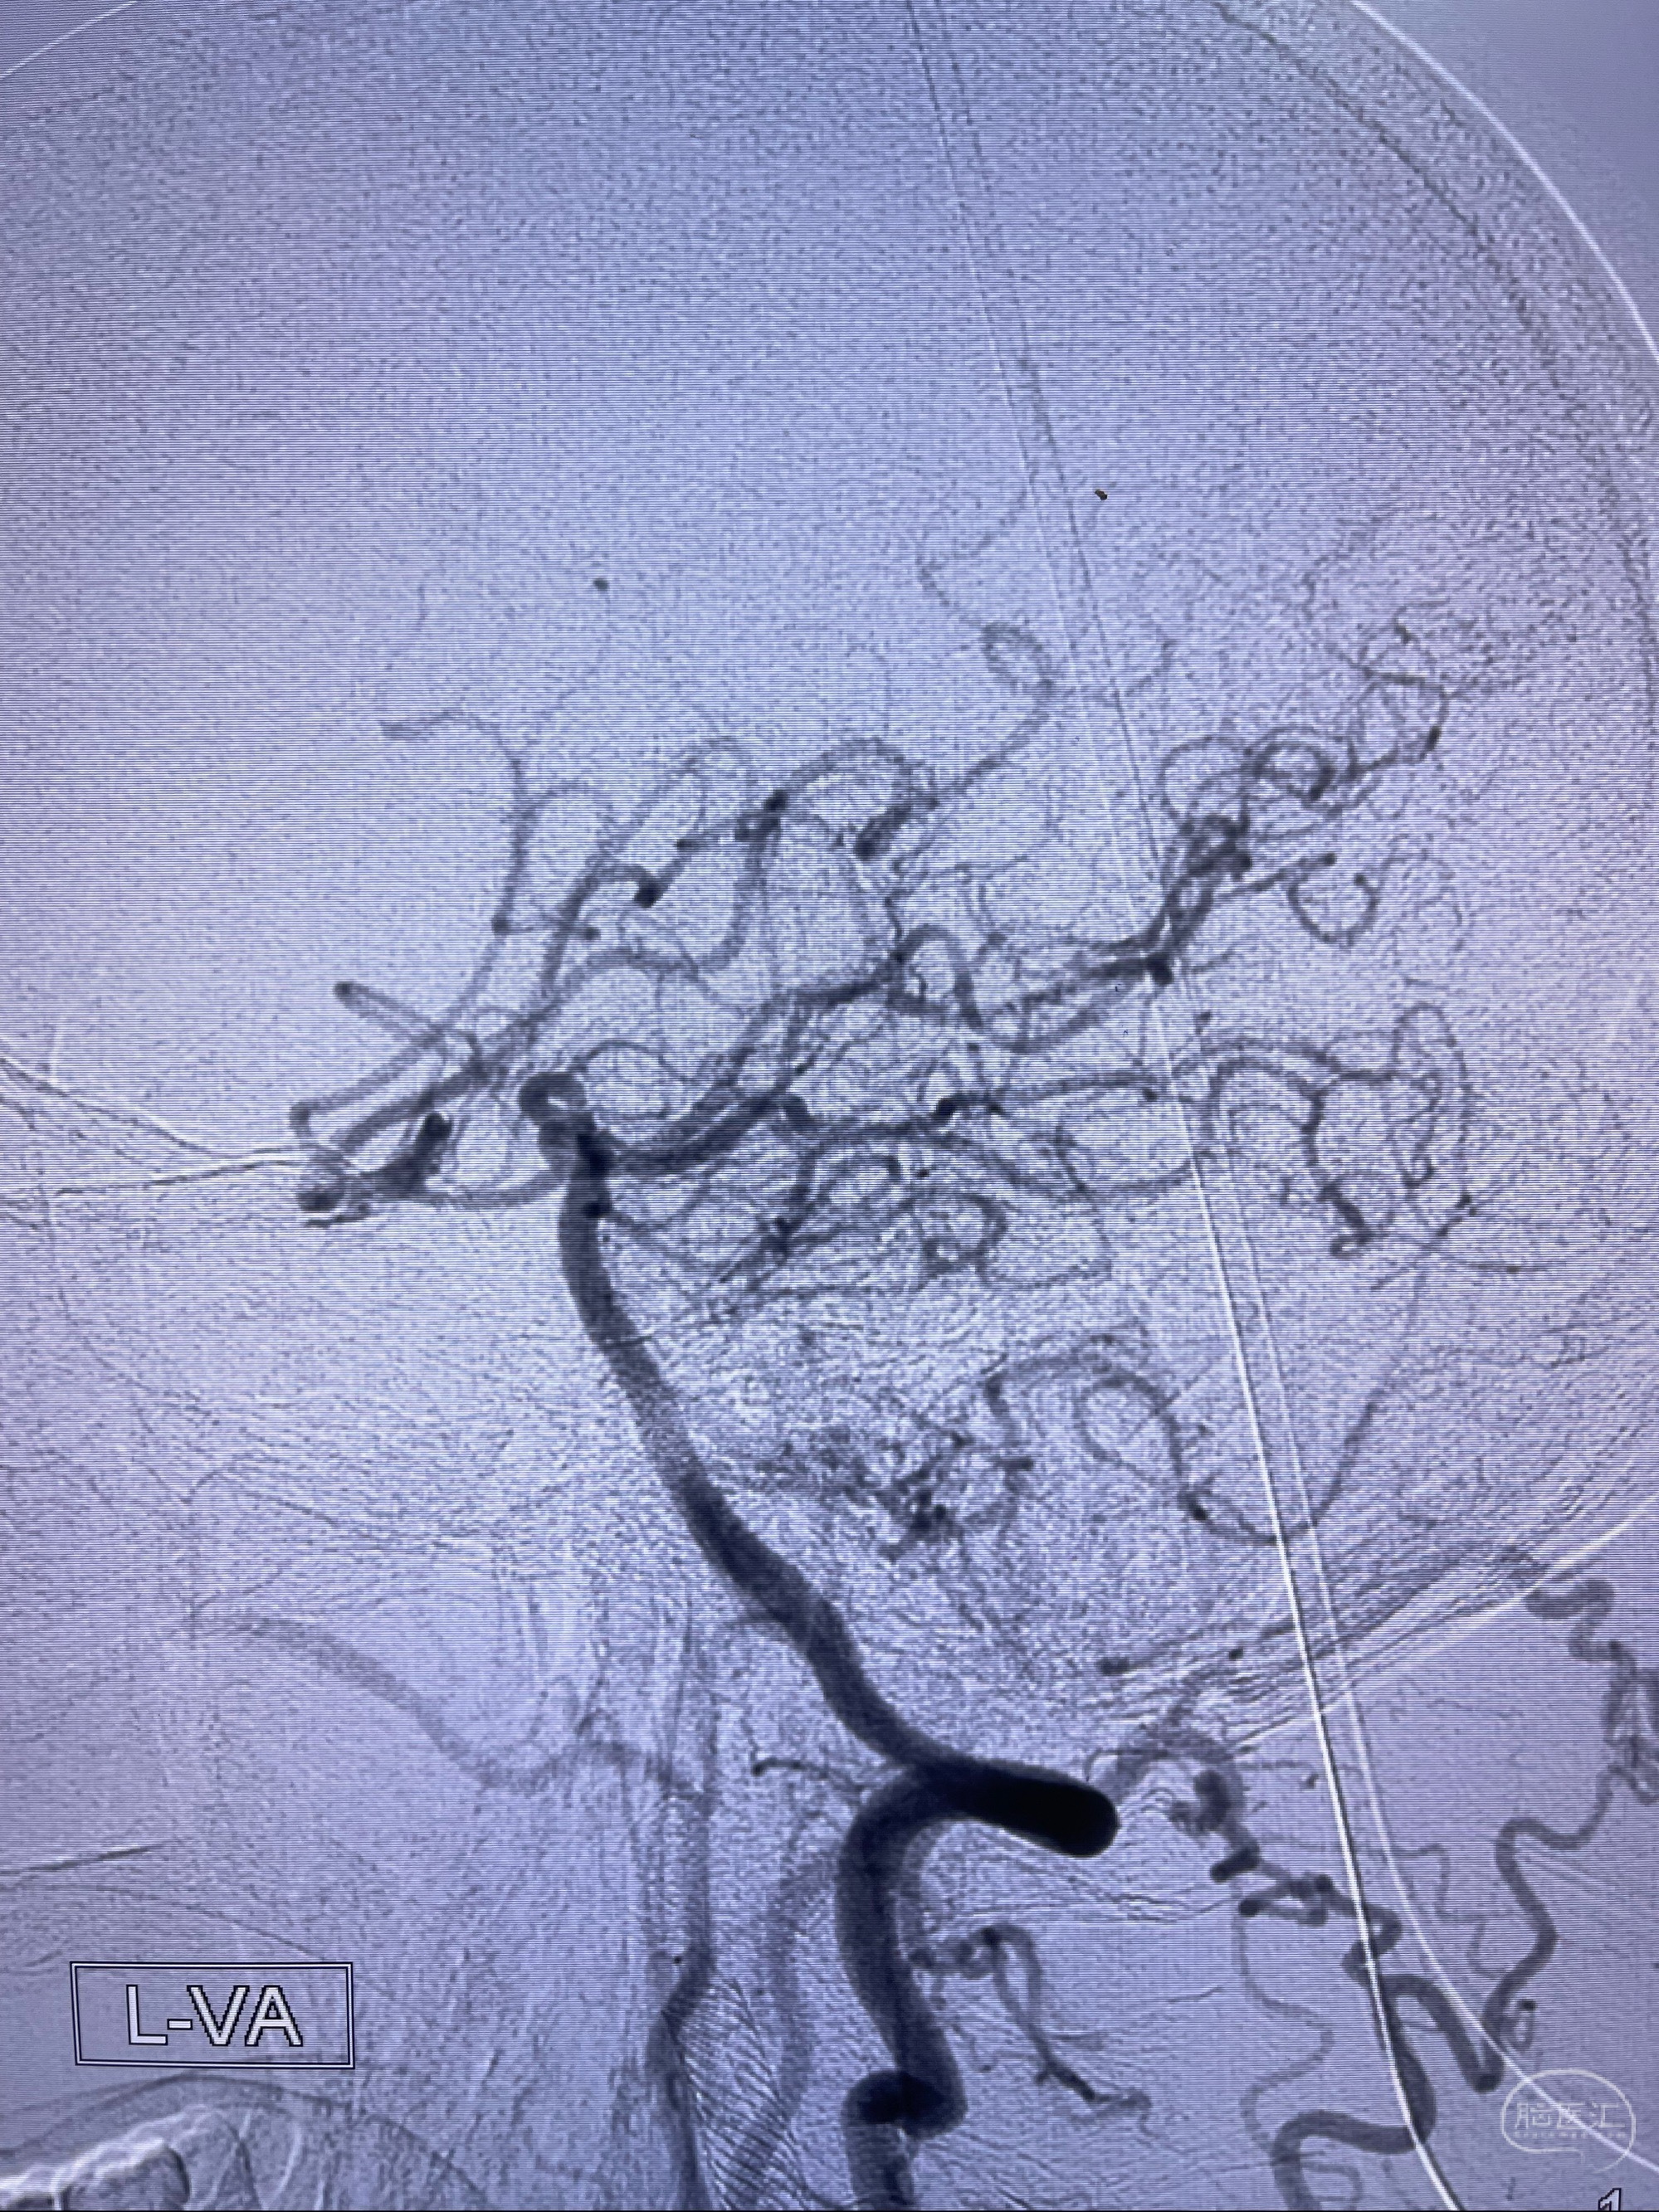

2023-07-10DSA:右侧颈内动脉岩骨段夹层伴中偏重度狭窄改变,左侧颈总动脉闭塞、右侧颈外动脉由右侧肋颈干甲颈干吻合代偿

左侧椎动脉可见代偿显示左侧前循环